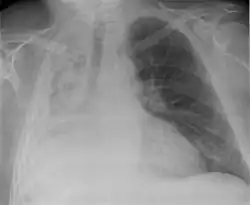

| Left tension pneumothorax with a large, well-demarcated area devoid of lung markings with tracheal deviation and movement of the heart away from the affected side. |

Tension pneumothorax

Tension pneumothorax is an emergent condition in which air gets trapped in the space between the chest wall and the lung. This space is referred to as the pleural space. Because air can't escape from this space, the air pocket grows larger and larger, resulting in the lung collapse closest to the pneumothorax. Forces are transmitted to the mediastinum and effectively "push" the mediastinal structures to the opposite side of the chest.[5]